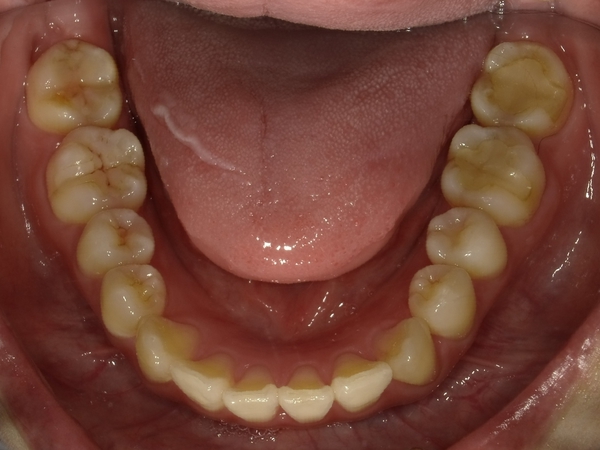

ガタガタとした歯並びや八重歯(叢生)CASE7